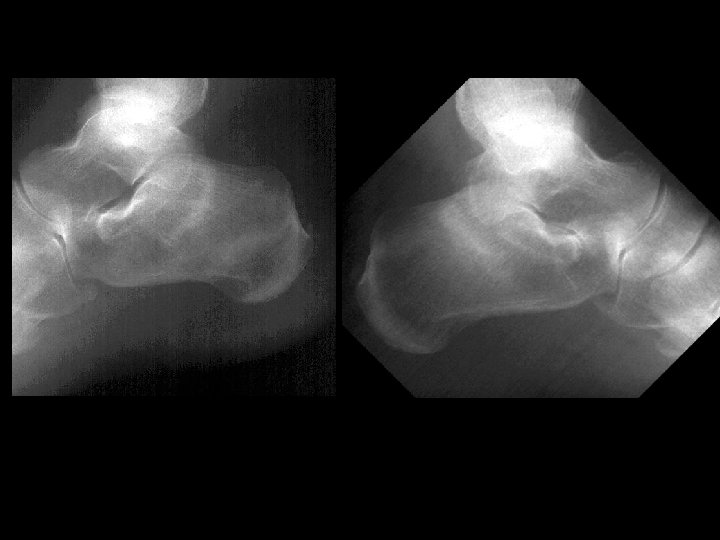

Bilateral calcaneous stress fractures • Findings: – Bone scan shows intense activity in both calcanei = non-specific – Plain films are diagnositic • ddx: – NONE! – This is an Aunt Minnie!